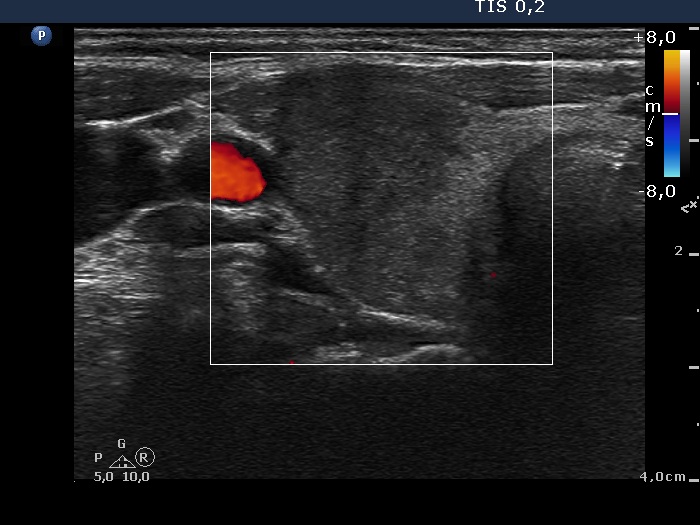

Initial examination (first row of images):

Ultrasonography: The thyroid presented with hypoechoic areas which had blurred borders. The echogenicity index was approximately 65% in the right and 20% in the left lobe. The thyroid was almost completely avascular.

Diagnosis: subacute, granulomatous de Quervain's thyroiditis.